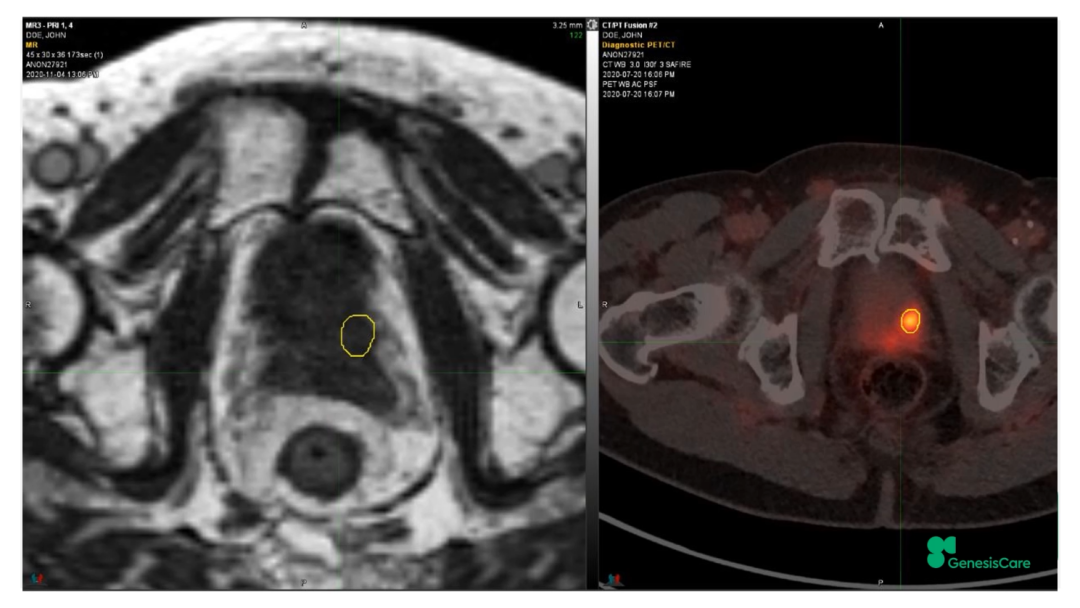

Dr. Camilleri介绍了一位72岁,在2006年接受了55Gy/20F放疗后复发的前列腺癌患者。当时它的PSA为28,局部晚期,期别为T3aN0M0。PET-CT显示前列腺左后部局部高代谢,活检也证实了这一点,并且活检结果表明肿瘤侵入左侧精囊腺底部。将其MRIdian MRI图像和PET-CT图像融合后,再根据活检结果确定靶区,见Figure 20-22,并制作放疗计划。放疗剂量为35Gy/5次,凝胶阻隔物很好地包含了直肠,见Figure 23,靶区和危及器官受量见Figure 24。患者于2020年12月接受治疗,他体质很好,在放疗期间和之后,坚持每周三次5公里跑步,始终未出现GU和GI毒性。他的PSA最低值为0.45,在2022年5月的随访数据中,睾丸激素水平回到了正常的33%。在2022年1月的放疗后PSMA PET的图像上,未见肿瘤高代谢见Figure 25。